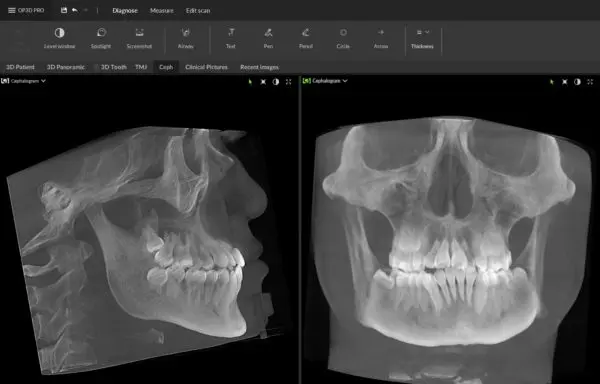

Productos y Servicios

Ofrecemos una amplia gama de equipos médicos, diseñados para satisfacer las necesidades de nuestros clientes y facilitar su trabajo.

Solo trabajamos con marcas de calidad, donde podemos ofrecer garantía, y alcanzar la excelencia en nuestro servicio.